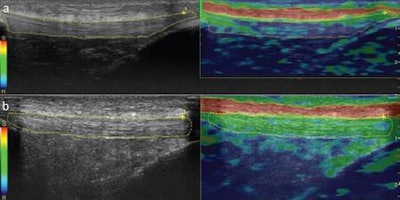

Real-time ultrasound elastography was also performed on the same regions to calculate strain ratio measurements. The scanner's software calculated the strain ratio measurements, coded the tissue strain in the selected region of interest on a scale between 1 (softest tissue, greatest strain) and 6 (hardest tissue, no strain), and then color-coded tendons based on elastographic patterns at the three measurement sites (grade 1, blue: hardest tissue; grade 2, blue/green: hard tissue; and grade 3, green: intermediate tissue).

There were also three additional color-coded subgrades -- subgrade a, no red coloring: homogeneous; subgrade b, parallel red stripes along the length of the tendon: relatively homogenous; and subgrade c, patchy distribution of color codes on the dominant tendon pattern: heterogeneous.